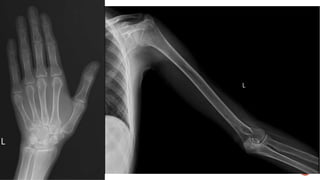

 AP and lateral radiographs of the skull show multiple tiny lucent areas with areas of

sclerosis in between, giving rise to salt and pepper skull appearance.

 Radiographs of both the legs, knees and left humerus show diffuse osteoporosis with

few well defined lytic areas.

 Radiograph of the hand shows osteoporosis with coarse trabeculations of the

phalanges with mild erosions along tteh radial aspect.

FINDINGS

 Osteopenia

 Subperiosteal resorption: classically along radial aspects of phalanges

 Floating tooth

 Subchondral resorption (lateral end of clavicles, pubic symphysis, sacroiliac joints)

 Subligamentous resorption(ischial tuberosity, trochanters)

 Brown tumors(more common in primary)

 Salt and pepper skull

 Rugger jersey spine